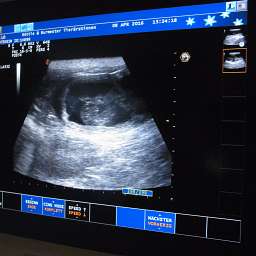

8.4.2016, 30.Tag: Heute ist ein großer Tag. Nicht nur für unsere kleine Mami Adele. Auch für uns und einige Menschen, die ihr kleines Wunder heiß ersehnen. Der Ultraschalltemin ist heute um 11.00Uhr. Hoffentlich hat Adele genug innere Ruhe und Ausgeglichenheit, um dem Stress adäquat begegnen zu können. Drückt bitte alle die Daumen. Unsicherheit scheint manchmal mein 2.Vorname zu sein...

18.00Uhr: Es ist vollbracht: "Lieber Nacho, wir dürfen Dir gratulieren. Du wirst Papa."

Mit pochendem Herzen durften wir 4 pochende Herzen unter Adeles pochendem Herzen sehen. Es ist immer wieder ein besonderer Moment. Das Wunder des Lebens nimmt seinen Lauf. Also, Ihr dürft Euch freuen: es sind mindestens 4 kleine Wunder unterwegs. Sucht Euch doch schon mal eins aus:

Adeles Gewicht aktuell 6,25Kilo.